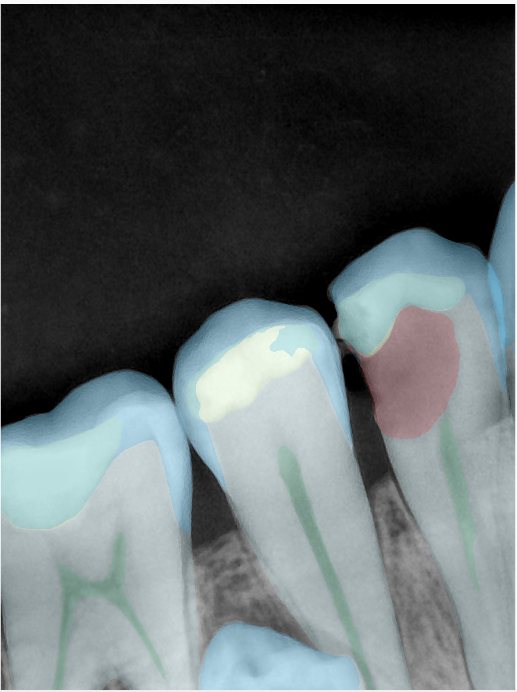

CR/DR 牙齿分割阶段记录

当前进展

- 完成了 CR/DR 牙齿相关分割训练

- 当前结果已经达到阶段预期,但仍有细节问题需要继续处理

相关测试

遇到的问题

- 训练过程中出现过 mask 下移问题

- 部分结果会出现 box 填充异常

- mask 边缘仍然有比较明显的锯齿感

第二版算法问题测试